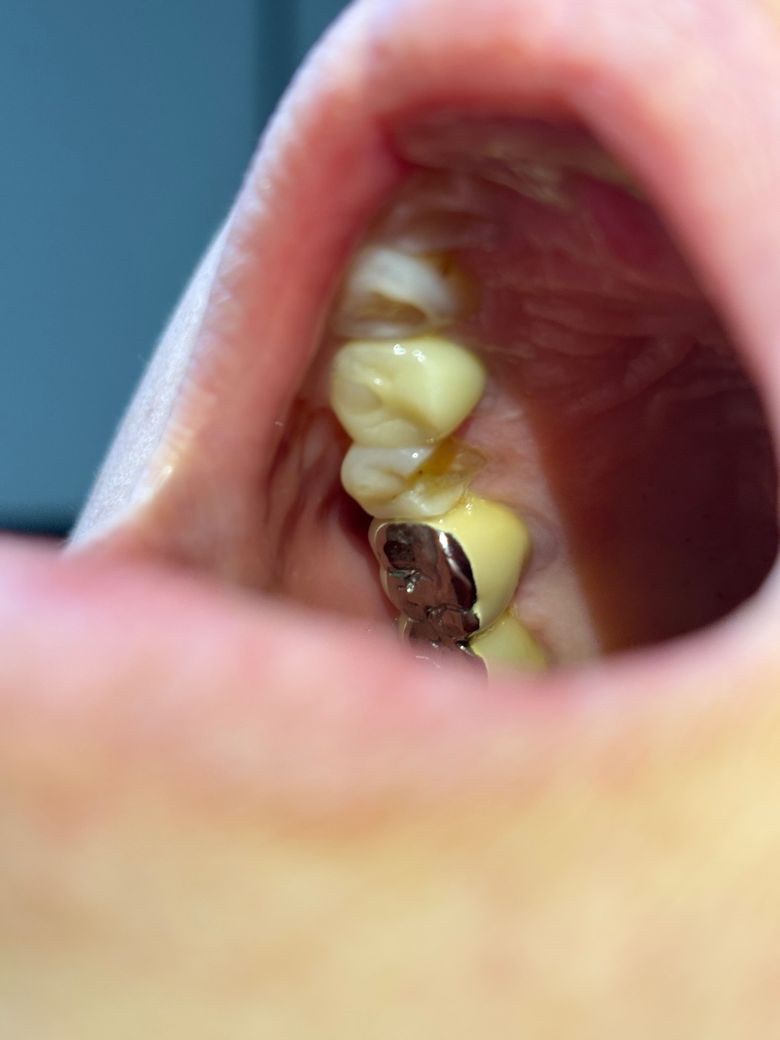

깨진 이 치아 크라운? 임플란트? 어떤게 더 낫나요

엄마 이가 갑자기 깨졌습니다.

살펴보니 (세로로?)치아 절반 정도가 날아갔더라구요ㅜㅜ

치과에서는 크라운 치료랑 임플란트 치료를 말씀주셨는데 깨진 부분 쪽 치아가 잇몸쪽에 남아있는게 거의 없어서 크라운은 치료하면 얼마나 사용할 수 있을지 모르겠다고 임플란트를 권장하셨습니다.

임플란트를 하려니 남아있는 이를 뽑아야한다는게 맘에 걸리고, 크라운을 하려니 치료 후 또 임플란트 치료까지 이중으로 해야할까봐 고민이 되네요.

사진으로 정확하게 확인은 어렵겠지만 그래도 다른 분들의 의견은 어떤지 듣고 싶어서 질문 남깁니다. 어떻게 치료하는 게 가장 좋은 방법일까요?

• 1번 째 사진